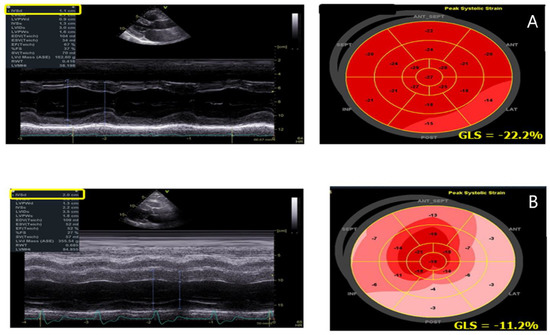

3. Speckle Tracking Echocardiography

- D’Andrea, A.; Radmilovic, J.; Ballo, P.; Mele, D.; Agricola, E.; Cameli, M.; Rossi, A.; Esposito, R.; Novo, G.; Mondillo, S.; et al. Left ventricular hypertrophy or storage disease? the incremental value of speckle tracking strain bull’s-eye. Echocardiography 2017, 34, 746–759. [Google Scholar] [CrossRef] [PubMed]

- Esposito, R.; Galderisi, M.; Santoro, C.; Imbriaco, M.; Riccio, E.; Maria Pellegrino, A.; Sorrentino, R.; Lembo, M.; Citro, R.; Angela Losi, M.; et al. Prominent longitudinal strain reduction of left ventricular basal segments in treatment-naïve Anderson-Fabry disease patients. Eur. Heart J. Cardiovasc. Imaging 2019, 20, 438–445. [Google Scholar] [CrossRef] [PubMed]

- Liu, D.; Hu, K.; Nordbeck, P.; Ertl, G.; Störk, S.; Weidemann, F. Longitudinal strain bull’s eye plot patterns in patients with cardiomyopathy and concentric left ventricular hypertrophy. Eur. J. Med. Res. 2016, 10, 21. [Google Scholar] [CrossRef]

- Esposito, R.; Santoro, C.; Sorrentino, R.; Riccio, E.; Citro, R.; Buonauro, A.; Di Risi, T.; Imbriaco, M.; Trimarco, B.; Pisani, A.; et al. Layer-specific longitudinal strain in Anderson-Fabry disease at diagnosis: A speckle tracking echocardiography analysis. Echocardiography 2019, 36, 1273–1281. [Google Scholar] [CrossRef]

| GLS | -Reduction in LV GLS with a prevalent involvement of the infero-lateral wall of the LV | -Correlates with LGE at CMR |